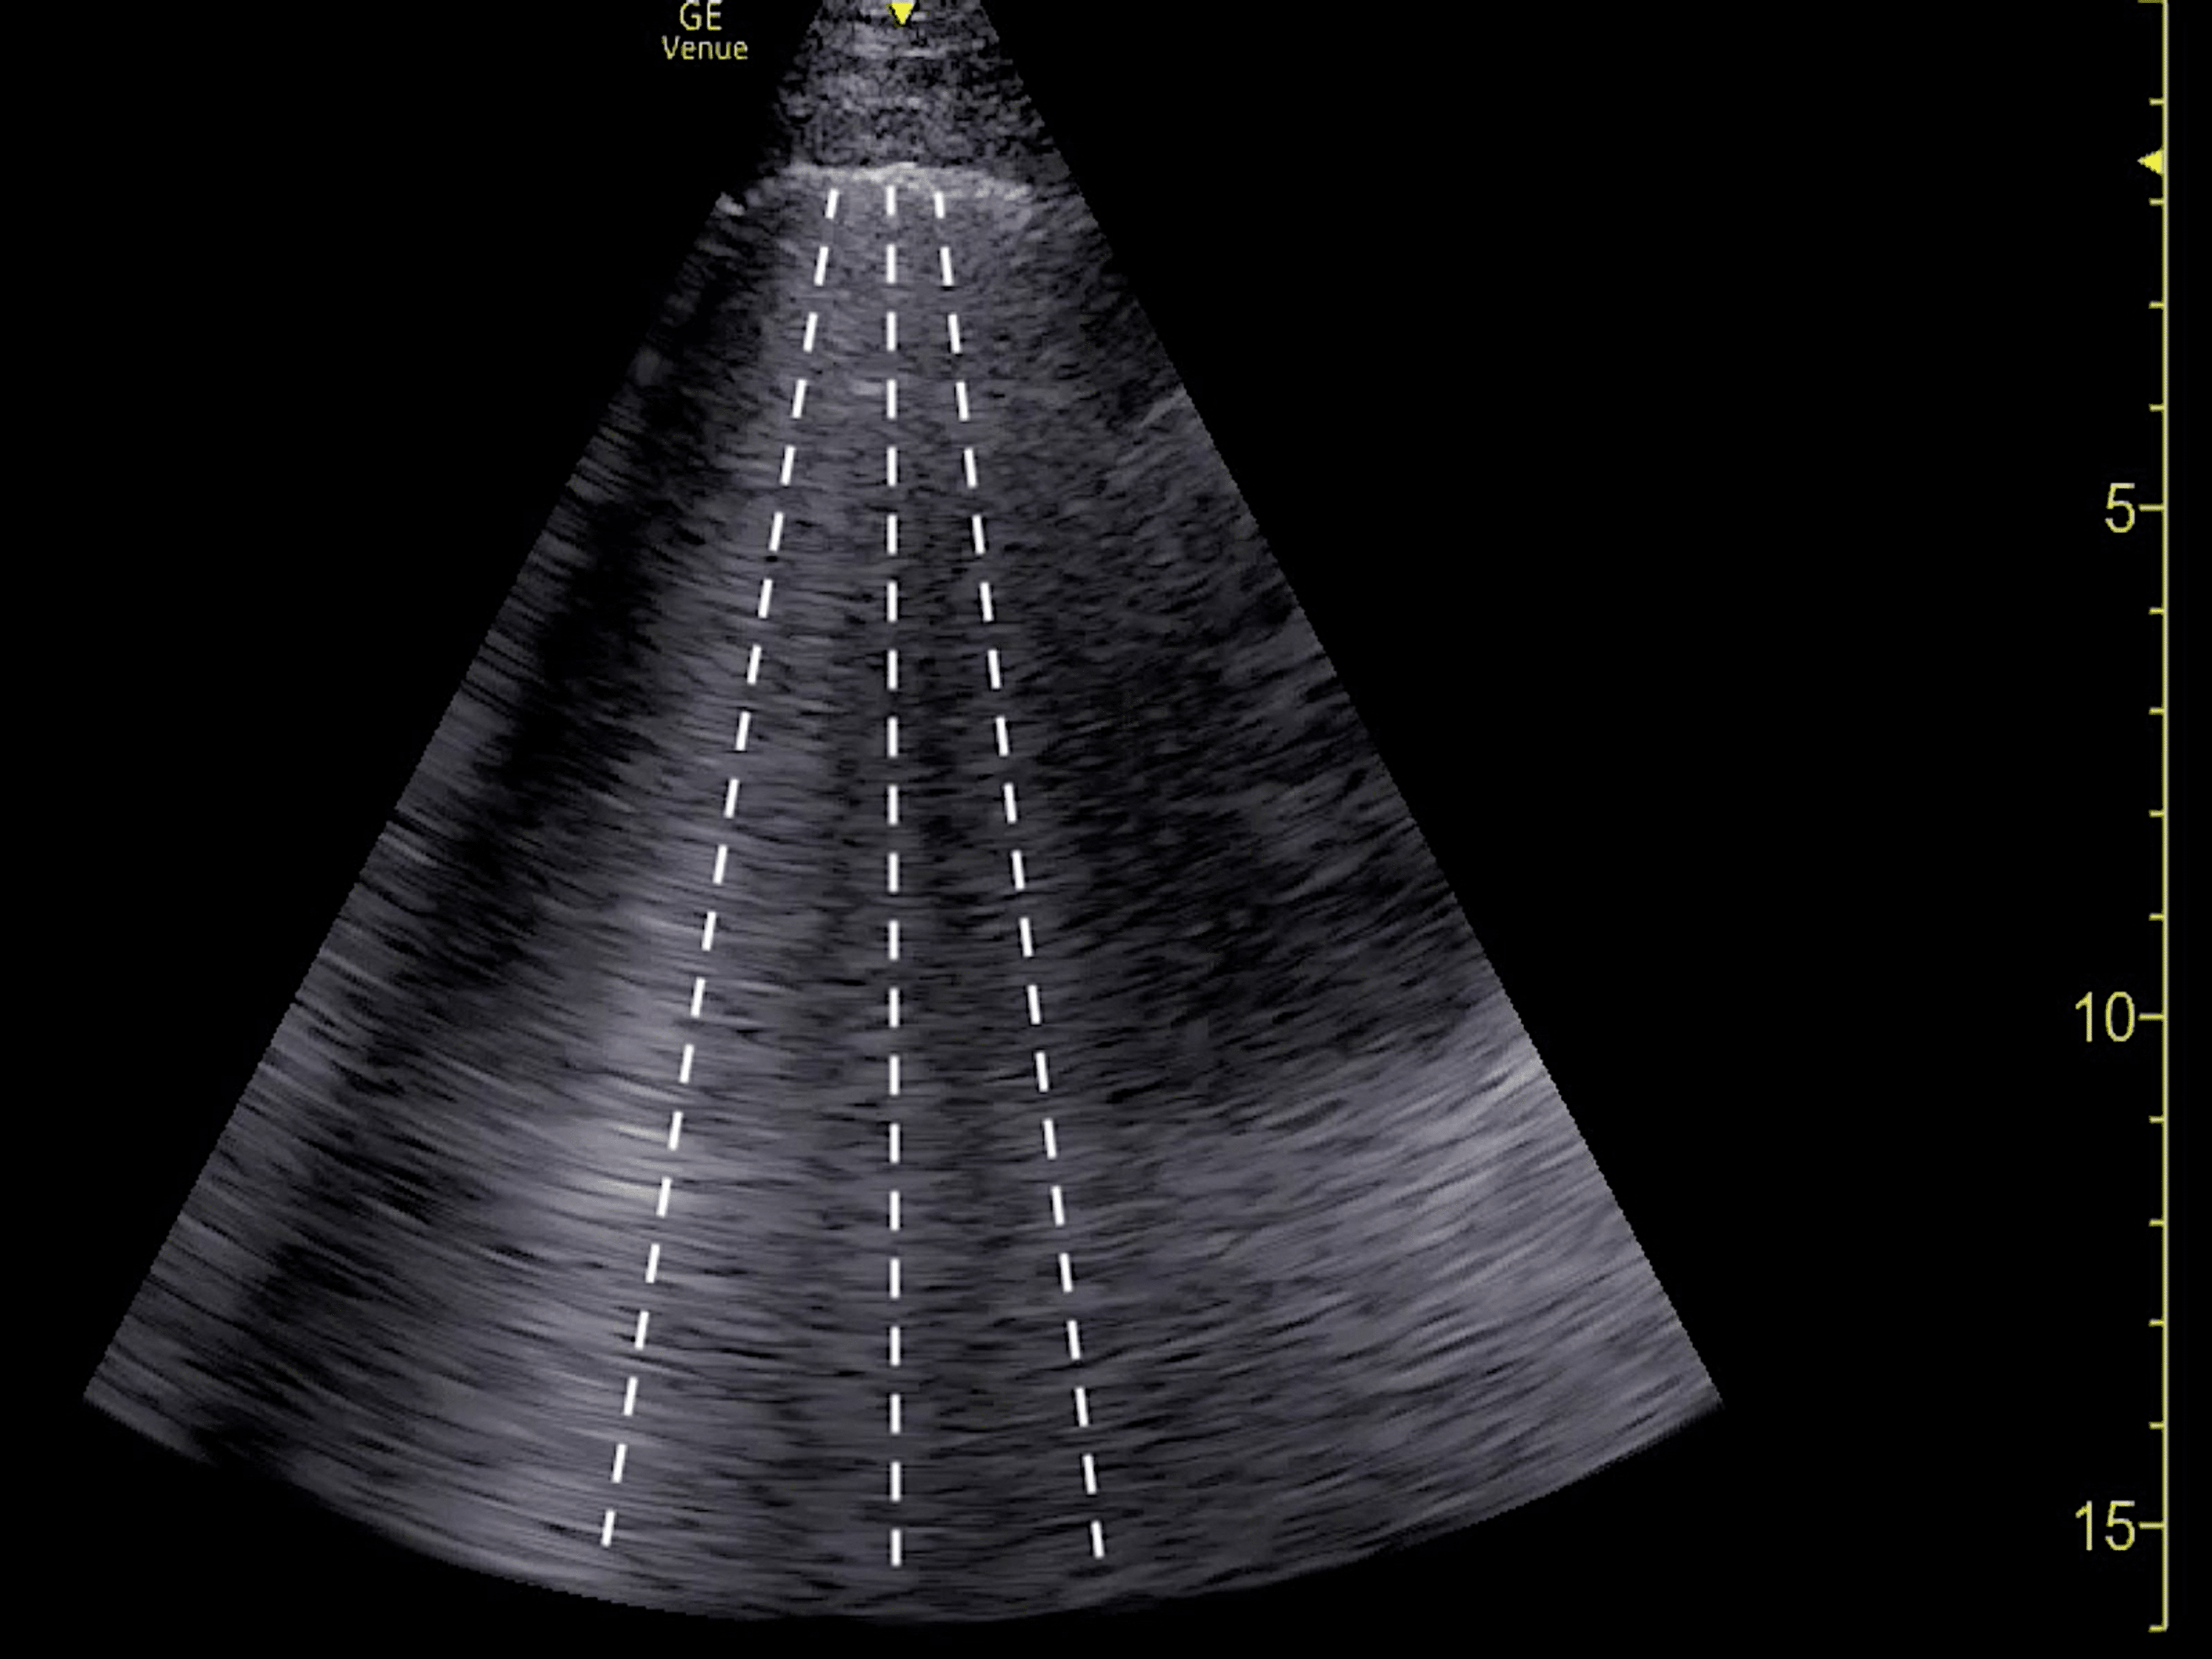

(a) Bedside transthoracic echocardiography, apical 4chamber view

(a) Bedside transthoracic echocardiography, apical 4chamber view Bedside Echocardiography Bedside echocardiography in the undifferentiated shortness breath can help elucidate cardiac failure vs. Cardiac ultrasound, or echocardiography, is a noninvasive diagnostic modality that can provide detailed. Bedside echocardiography has been shown to be very useful at detecting whether true cardiac contractility is occurring (100, 101). For the emergency management of cardiovascular disorders, echocardiography and thoracic ultrasound are indispensable imaging. Bedside Echocardiography.